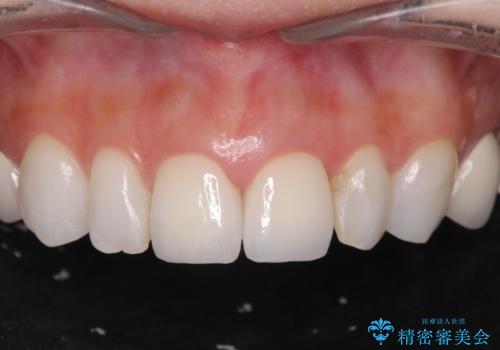

歯の大きさの不揃いが改善されただけでなく、色調もよくなり審美性をしっかりと改善することができました。